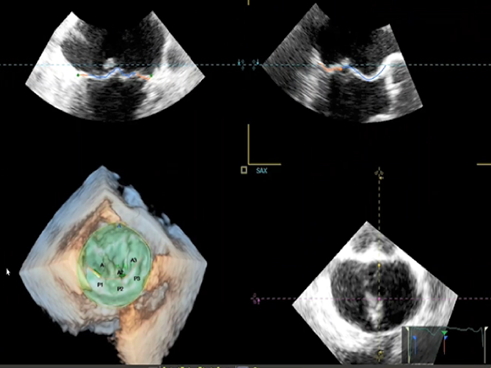

影像,火眼“晶”睛

飞利浦国产EPIQ 7C带来业内首创的TrueVue技术:TrueVue Light光源心腔镜,光影变化,可透过表面看本质,真实还原心脏立体结构,协助准确诊疗;TrueVue Color彩色心腔镜,血流溯源,更直观、准确的显示心脏血流动力学形态,带来全方位的极致体验。

图片

TrueVue Light光源心腔镜

TrueVue Color彩色心腔镜